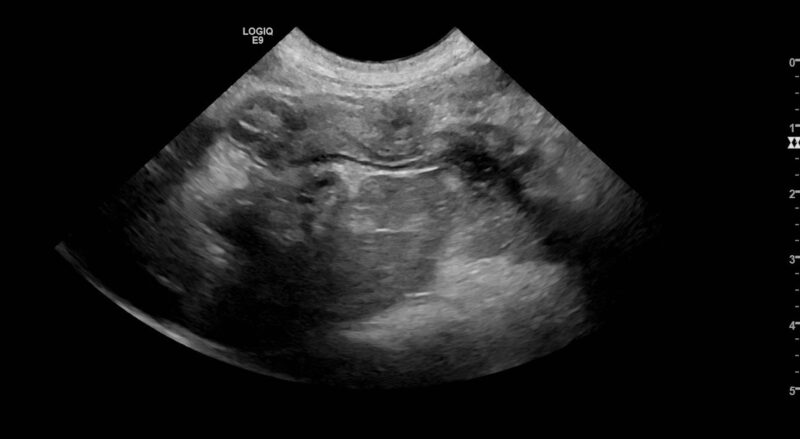

Pankreatitis ist eine Diagnose, die im Praxisalltag schnell im Raum steht: Das klinische Bild ist oft unspezifisch, Ultraschallbefunde sind nicht immer eindeutig und ein erhöhter Lipasewert wirkt zunächst wie eine einfache Erklärung. Genau hier liegt jedoch das Problem: Lipasen sind wertvolle diagnostische Werkzeuge, aber keine eindeutigen „Ja-/Nein-Marker“. Die Diagnose Pankreatitis ergibt sich immer aus der Kombination von Klinik, Labor und Bildgebung – häufig ergänzt durch Verlauf und Therapieansprache.

Gerade wegen der unspezifischen Klinik wird häufig der Lipasewert herangezogen. Wichtig ist jedoch: Lipasen sind nur ein Baustein im diagnostischen Werkzeugkasten. Das gilt im Übrigen auch für den Ultraschall, der zwar unverzichtbar ist, aber ebenfalls nicht allein entscheidend interpretiert werden darf. Zudem zeigt ein erhöhter Lipasewert nicht, ob es sich um eine primäre Pankreatitis handelt oder um eine sekundäre Reaktion des Pankreas, beispielsweise im Zusammenhang mit einer Enteropathie, einer systemischen Erkrankung oder anderen entzündlichen Prozessen.

Der diagnostische Dreiklang bleibt entscheidend: Klinik, Labor und Ultraschall. Ein häufiger Stolperstein sind erhöhte Lipasen ohne klinische Symptome, etwa im Rahmen von Routineprofilen. Positive Testergebnisse können auch bei klinisch gesunden Tieren vorkommen und sollten daher nicht automatisch als krankheitsrelevant gewertet werden. Zudem können zahlreiche Erkrankungen mit erhöhten Lipasewerten einhergehen, darunter chronische Enteropathien, Herz- oder Perfusionsstörungen, systemische Infektionen oder endokrine Erkrankungen. Bei Katzen mit Diabetes mellitus wurden in Studien beispielsweise häufig erhöhte PLI-Werte festgestellt, ohne dass zwingend eine klinisch relevante Pankreatitis vorlag. Gerade deshalb lohnt sich bei moderaten Lipaseerhöhungen oft der Blick auf mögliche Begleiterkrankungen. Nicht selten reagiert das Pankreas lediglich sekundär auf ein anderes primäres Geschehen.